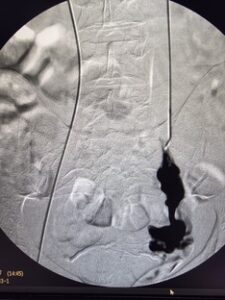

Η θεραπεία εκλογής για το σύνδρομο πυελικής συμφόρησης είναι η ενδαγγειακή αποκατάσταση με τη χρήση ελασμάτων (coils). Ουσιαστικά, πρόκειται για μια ελάχιστα επεμβατική μέθοδο, που αποσκοπεί στην κατάργηση των προβληματικών φλεβών με αρκετά ικανοποιητικά αποτελέσματα. Πρόσφατα, δημοσιεύτηκε στις κατευθυντήριες οδηγίες της Αγγειοχειρουργικής κοινότητας και στο Αμερικάνικο φλεβολογικό Forum, ως προτεινόμενη θεραπεία για την αντιμετώπιση της νόσου , η ενδαγγειακή αποκατάσταση με εμβολισμό.

case 1

φλέβας με ύφεση συμπτωματολογίας